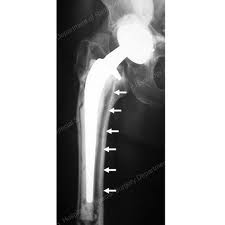

Osteolysis is a problem that causes the bone surrounding the implant to seemingly ‘melt away’. The weakening of bone around the hip replacement is seen on x-rays, and looks as though there are holes in the bone around the joint replacement. Because of the weakened bone, the hip replacement become loose, and begins to wobble within the bone. Patients experience symptoms of pain and limitations in motion of the hip. The technical name for this weakening of bone is called osteolysis.

Osteolysis occurs as a result of wearing out of the parts of the hip replacement. Over years of use, microscopic fragments of the hip replacement cause irritation to the tissues around the implant, and begin to cause the weakening of bone. Even though modern hip replacements are made of materials that can withstand wearing out very well, even small amounts of these microscopic particles can damage the bone around the hip replacement.